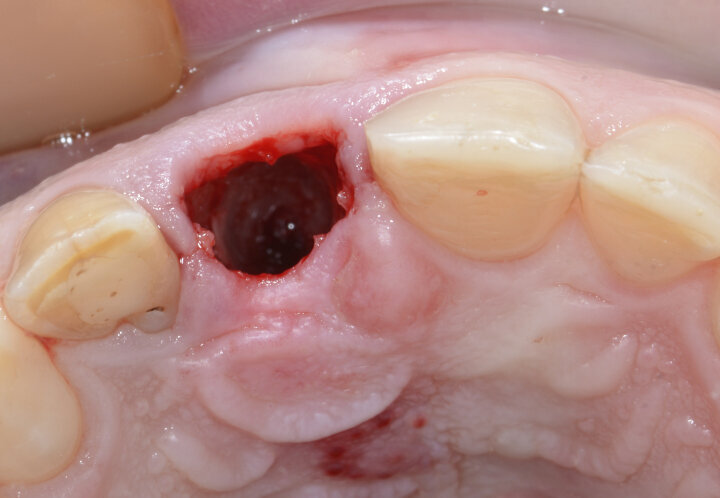

Fig. 11: Clean socket after atraumatic extraction of tooth #11.

After precise planning, the tooth was extracted. At the resorption and fracture area of tooth #11, granulation tissue was clearly visible (Fig. 9). The granulation tissue was removed with an Er:YAG laser (H14 handpiece, Fotona; Fig. 10). The extraction was atraumatic and the socket clean and ready for implant placement (Fig. 11).